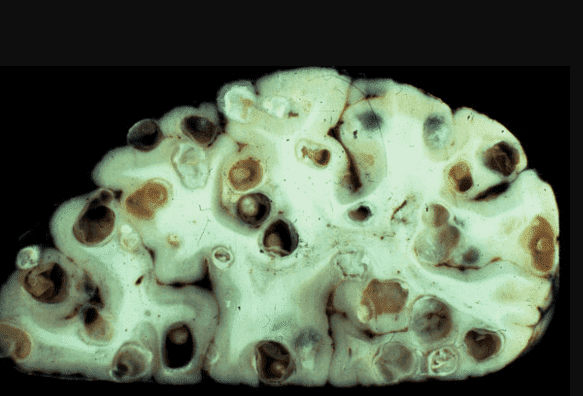

На фото нижче можете побачити знімок кишечника. Пацієнтка померла від раку кишківника, спричиненого паразитами. Паразити отруюють здорові клітини своїми токсинами, через що вони змушені перероджуватися, змінювати свою структуру. І перероджуються вони саме в ракові клітини, які агресивніші й здатні протистояти паразитам. Але для людини ці клітини згубні. Пухлина швидко розвивається і метастазує. Людина гине протягом лічених місяців.

"Ходи" паразитів у просвіті кишечника